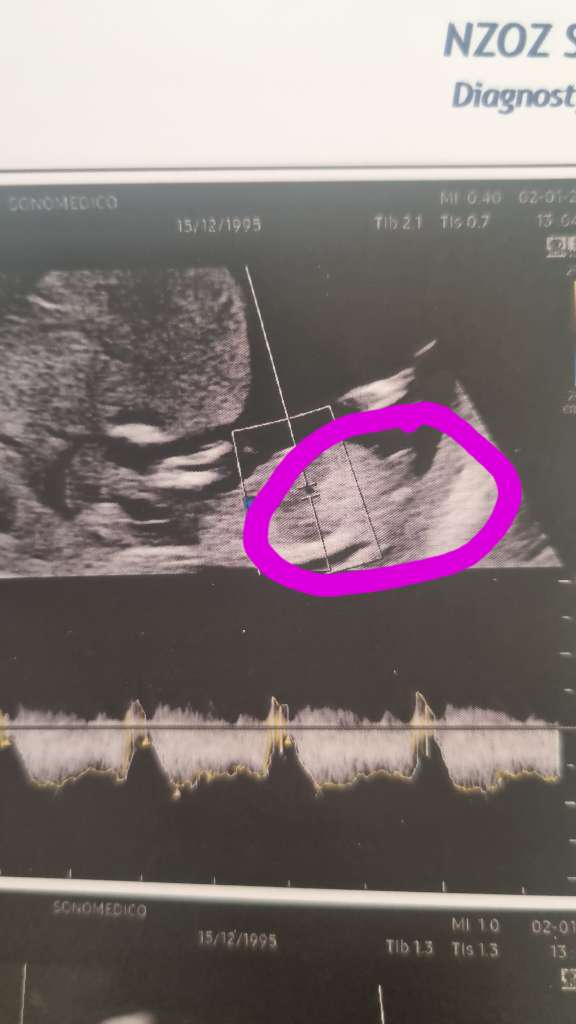

Witam, pewnie są tu też bardziej ode mnie doświadczone mamy. Dziś miałam badanie prenatalne i nie pytałam o płeć dziecka ale dostałam zdjęcia usg , na którym widać wyrostek . Jaką płeć obstawiacie ? Wizytę mam 19 stycznia ,może dzieciątko się wtedy pokaże i dam też znać